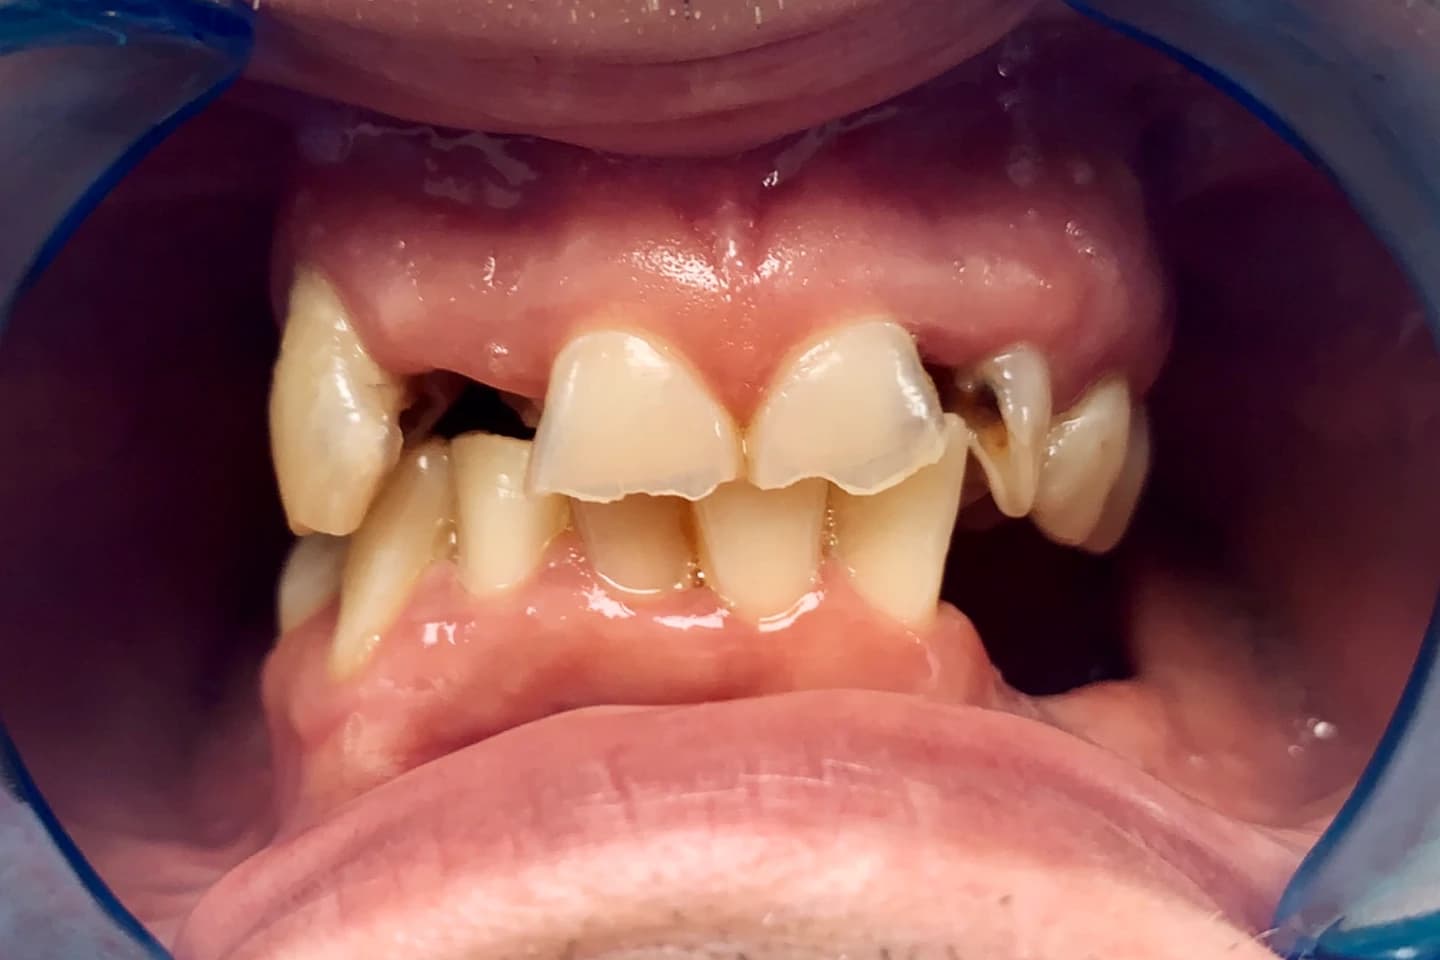

Osmeh i oblik zuba slike - pre i posle

Stomatološka ordinacija Marco Dental Tourism svakodnevno stvara neverovatne transformacije osmeha. Pogledajte galeriju naših radova i uverite se u moć stomatologije!

Želimo i vama da pomognemo da postignete savrršen osmeh kada su u pitanju položaj i oblici zuba. Zato smo prikupili inspirativne priče i fotografije zuba naših pacijenata, koje će vam pokazati šta je sve moguće uz stručnost i posvećenost našeg tima.